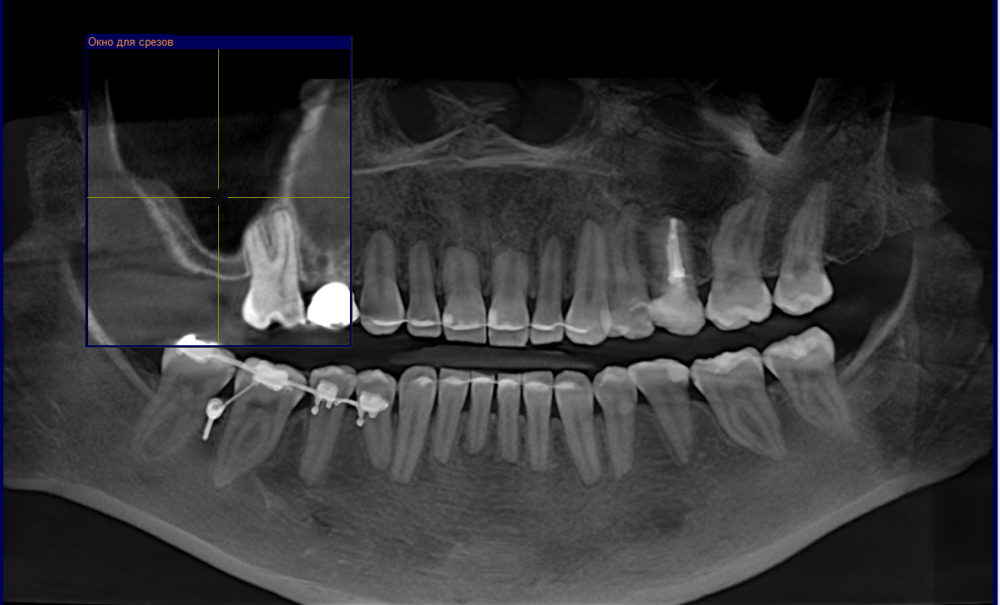

Ания Опубликовано 27 февраля, 2023 Поделиться Опубликовано 27 февраля, 2023 Необходим открытый синус лифтинг, что лучше выбрать, аутогенный трансплантат или ксенотрансплантат? Доктор предупредил, что аутогенный может на выходе дать недостаточную высоту. Нашла статью ваших западных коллег про ксенотрансплантаты, пишут о серии случаев возникновения проблем 2-13 лет позднее удачно проведенных операций. По списку проблемы: патологии пазух и верхнечелюстной кости, смещение материалов трансплантата, ороантральные коммуникации, несостоятельность имплантата, реакции на инородное тело, инкапсуляция, хроническое воспаление, фенестрации мягких тканей и связанные с ними кисты. Там есть фото, можно посмотреть даже если английским не владеете, https://www.ncbi.nlm.nih.gov/pmc/articles/PMC6737859/#!po=16.4286 У меня аутоимунное заболевание в ремиссии, я с ним мучилась более 2 лет,и мне очень бы не хотелось каких-то проблем снова. как грамотно оценить риски обоих вариантов для регенерации? Ссылка на комментарий